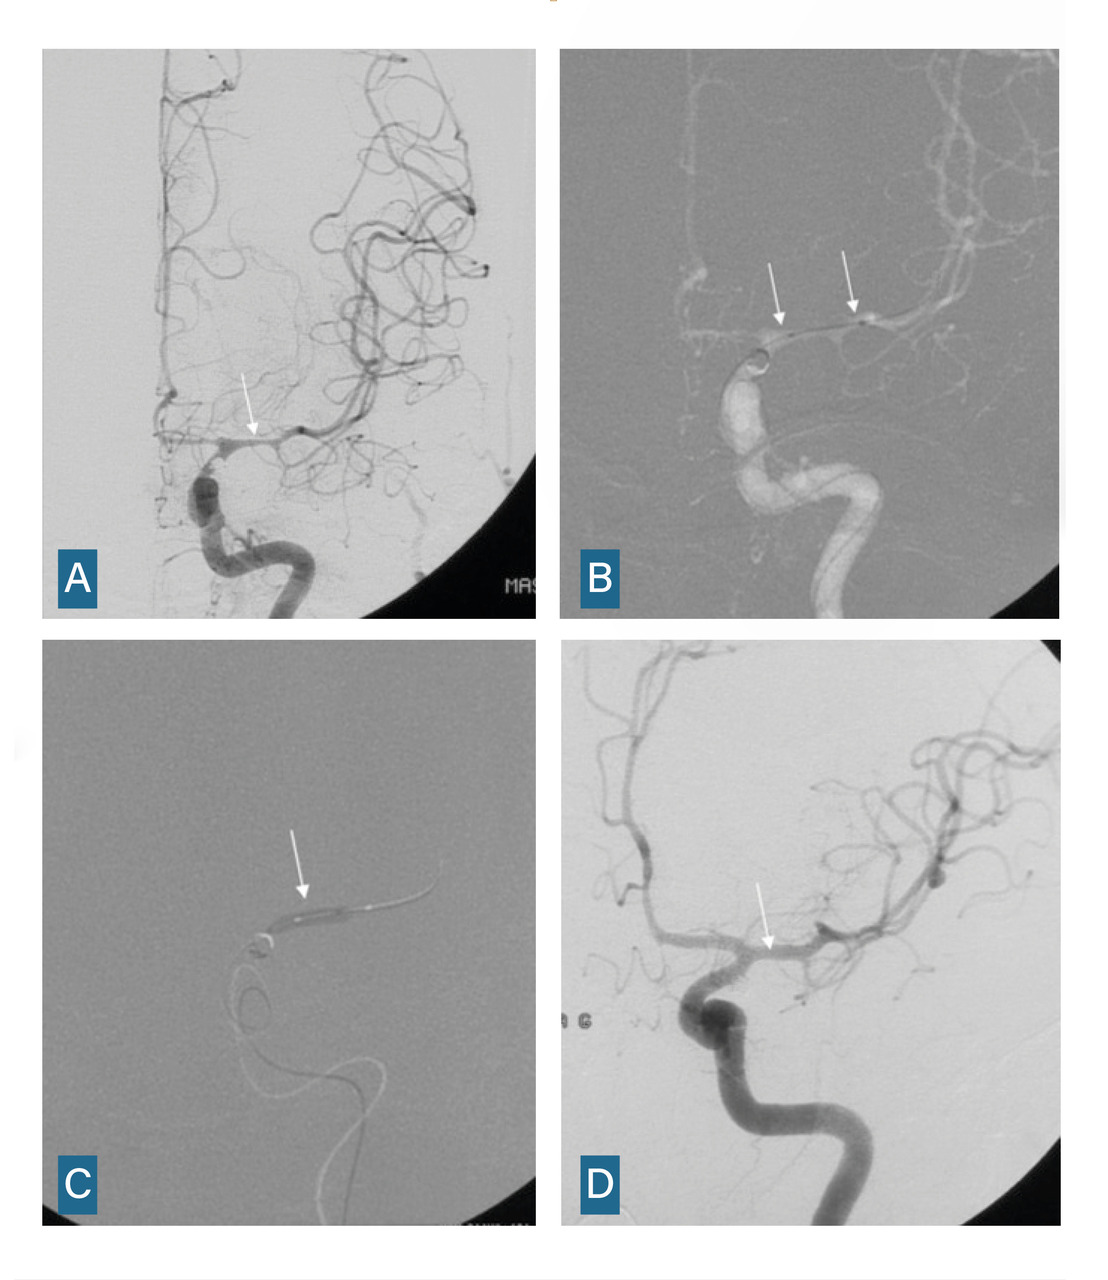

L’imagerie cérébrale intervient également dans le suivi et la prise en charge des complications tardives. En cas de vasospasme résistant au traitement ­médical optimal, une procédure endo­vasculaire est menée, incluant une dilatation chimique et éventuellement mécanique (fig. 5).